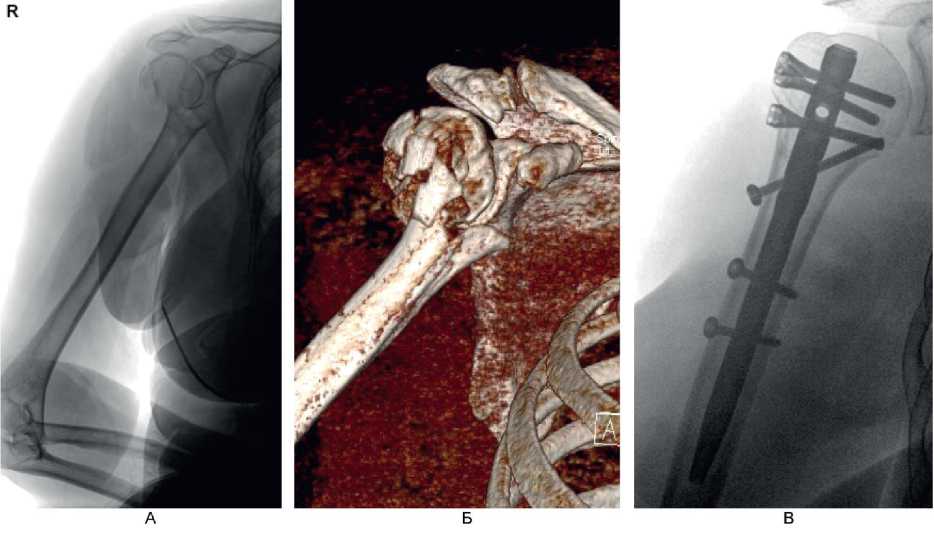

На контрольном осмотре через 6 мес у 7 (63,6 %) пациентов этой группы отмечено полное восстановление функции в плечевом суставе, у 4 (36,4 %) больных – небольшое ограничение движений и боль при движениях. Клинический пример 1. Больная М., 60 лет, поступила во ВЦЭРМ им. А.М. Никифорова в экстренном порядке. При поступлении выполнены рентгенография плечевого сустава в стандартных проекциях (рис. 6А) и компьютерная томография (см. рис. 6В). Перелом по классификации АО – В3. На 2-е сутки после поступления выполнено оперативное вмешательство – БИОС перелома хирургической шейки правой плечевой кости (см. рис. 6В).

Рис. 6. Больная М., 60 лет. А – рентгенография; Б – компьютерная томография поврежденного сегмента конечности; В – контрольная рентгенография в 1-е сутки после операции (косая проекция)

Клинический пример 2. Больной А., 50 лет, поступил в клинику ВЦЭРМ им. А.М. Никифорова в экстренном порядке. Выполнены рентгенография плечевого сустава в стандартных проекциях (рис. 8А), и компьютерная томография (см. рис. 8Б).

Рис. 8. Больной А., 50 лет. А – рентгенография плечевого сустава в стандартных проекциях; Б – компьютерная томография до операции

Перелом по классификации АО – С3.1. На 2-е сутки после поступления выполнено оперативное вмешательство – БИОС хирургической шейки правой плечевой кости. Рентгенография на 1-е сутки после операции представлена на рис. 9А, Б, контрольная рентгенография плечевого сустава через 6 мес после операции – на рис. 9В. Функциональный результат после операции – на рис. 10.

Рис. 9. Больной А., 50 лет. А, Б – рентгенография на 1-е сутки после операции; В – через 6 мес после операции